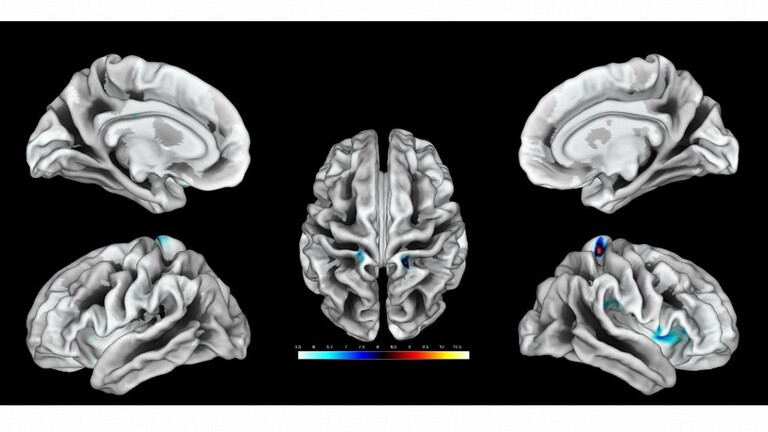

وبحثت الدراسة مرحلة إزالة أو نزع الاستقطاب في القشرة الدماغية البشرية وقدمت فهما أفضل لكيفية استجابة الدماغ لنفاد الطاقة، حيث قدمت لأول مرة فهما كاملا حول الفيزيولوجيا الكهربية للموت الذي يحدث عقب توقف الدورة الدموية في الدماغ البشري.

وأشار المقال إلى وجود دراستين جديدتين ستنشران في مجلة “Brain” العلمية، قام بهما فريق من العلماء كجزء من دراسة كبيرة تركز على مرحلة إزالة الاستقطاب في الدماغ، حيث وصف العلماء لأول مرة مرحلة “الموجة الكهربائية” للموت الدماغي.

وقال درير إن انتشار عمليات إزالة الاستقطاب أو “تسونامي الدماغ”، تعتبر بجميع المقاييس من أكبر الأحداث التي تصيب الدماغ الحي، وهي أشد من نوبات الصرع وتتعلق بالتغيرات الأيونية وتغيرات الناقل العصبي والتغيرات الكهربية والعديد من الجوانب الفيزيولوجية المرضية الأخرى التي تصيب الدماغ، وترتبط بتدفق كمية هائلة من الماء إلى الخلايا العصبية، مما يؤدي إلى تضخمها.

إلى ذلك، ذكرت الدراسة أن “هذه الموجة المنتشرة القابلة للعكس والتي يمكن عكسها تبدأ عادة بعد 2 إلى 5 دقائق من ظهور نقص التروية الحاد، مما يشير إلى بداية تغير عصبي سام يؤدي في النهاية إلى إصابة لا رجعة فيها”.

وأجرى العلماء تسجيلات من خلال تركيب شرائط أو صفائف قطب كهربائي لدى المرضى الذين تعرضوا لتلف دماغي حاد أدى إلى دخولهم في حالة لا رجعة منها أو ميؤوس منها تستوجب فقط بعض العلاجات التخفيفية بدون وجود فرصة للإنعاش.